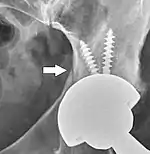

Hip prosthesis displaying aseptic loosening (arrows)

On radiography, it is normal to see thin radiolucent areas of less than 2 mm around hip prosthesis components, or between a cement mantle and bone. These may indicate loosening of the prosthesis if they are new or changing, while areas greater than 2 mm may be harmless if they are stable.[31] The most important prognostic factors of cemented cups are absence of radiolucent lines in DeLee and Charnley zone I, as well as adequate cement mantle thickness.[32] In the first year after insertion of uncemented femoral stems, it is normal to have mild subsidence (less than 10 mm).[31] The direct anterior approach has been shown to itself be a risk factor for early femoral component loosening.[33][34][35]